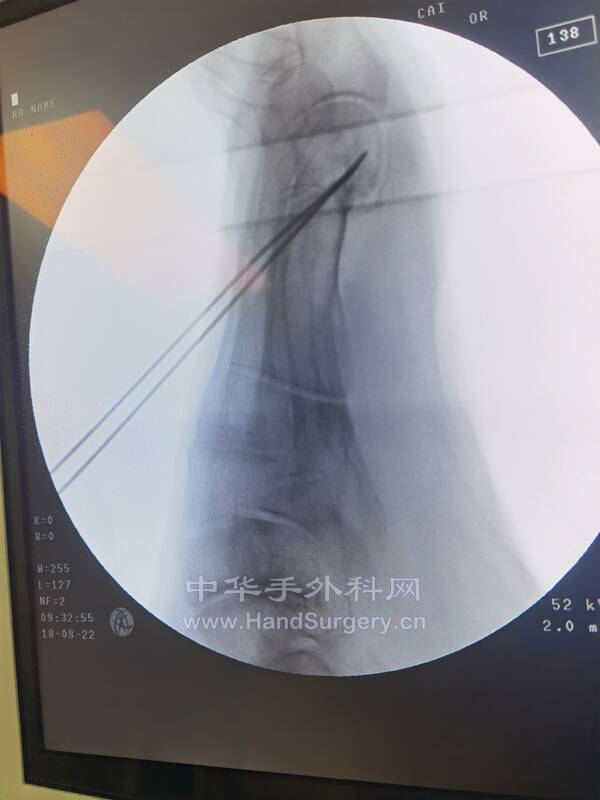

今日参观刘主任踇外翻手术1台,跟刘老师上台手术3台:右足第3趾肿物,右右拇趾肿物,双足踇外翻,刘老师细心教我们很多手术细节,很好的老师!